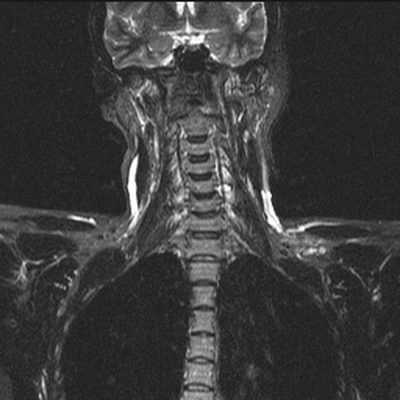

МРТ шеи: оценка сколиоза (коронарная плоскость, Т2 последовательность, STIR)

Боль в шее может быть вызвана проблемой в самом позвоночнике или в окружающих его мышцах. Наиболее часто дискомфорт в данной анатомической области обусловлен остеохондрозом, грыжей или протрузией межпозвонковых дисков, компрессией нервно-сосудистых пучков, иннервирующих спинной мозг, невралгией. Перед тем, как сделать выбор в пользу МРТ, врач оценивает характер боли и ее локализацию. Неприятные ощущения в области передней части шеи чаще свидетельствуют о заболевании трахеи, гортани, щитовидной железы, воспаленных лимфатических узлах, осложнениях со стороны уха. Для постановки диагноза в описанных ситуациях иногда достаточно проведения физикального и инструментального осмотра, ультразвуковой сонографии. Если пациент предъявляет жалобы на боль в задней поверхности шеи, усиливающуюся при повороте или наклоне головы, прострелы, ограничение в подвижности - для обнаружения проблемы обосновано сделать МРТ шейного отдела позвоночника. Магнитно-резонансное сканирование показывает структурные изменения в области интереса. Если боль носит функциональный характер, например, сопутствует миозиту, лучевая диагностика будет малоинформативна.